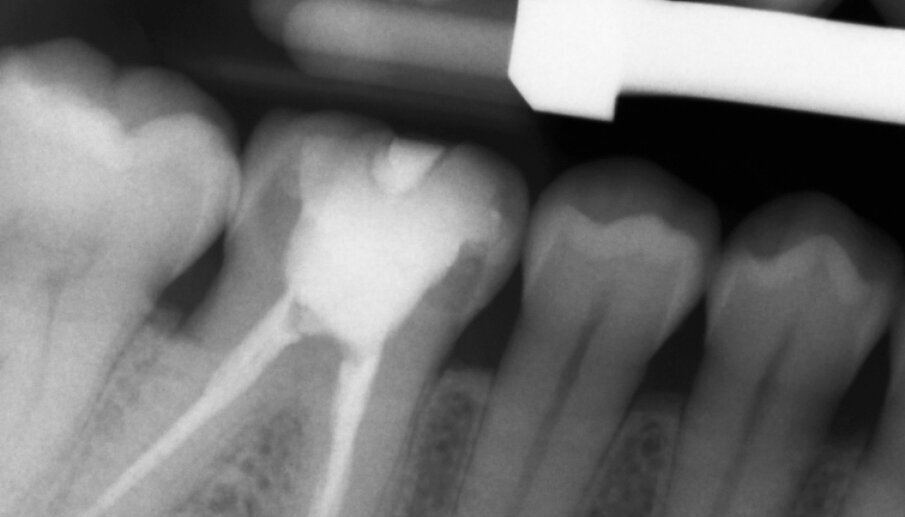

Figs. 13a & b: Radiographic control images before and after the treatment.

A 45-year-old male patient presented to the practice with a restoration on tooth #46. The tooth had been endodontically treated and temporised with a filling (Fig. 1). The temporary was removed, the tooth built up with Tetric N-Ceram Bulk Fill (Ivoclar Vivadent) and then prepared for the crown restoration (Fig. 2). An impression was taken with a one- step, two-phase impression technique using a putty and light-body silicone. After scanning the model, the crown was designed in the software suite (inLab, Dentsply Sirona) and milled from an IPS e.max CAD lithium disilicate block (Ivoclar Vivadent; Figs.3a & b). After the crystallisation fir- ing, the crown was stained and glazed (Fig. 4). The next step was to etch and silanate the ceramic crown with the new glass-ceramic primer Monobond Etch & Prime (Ivoclar Vivadent). This primer combines a ceramic etching and silanating component in a single material and therefore eliminates the need for the ceramic to undergo hydrofluoric acid etching (Fig. 5). After the etching and silanating step, the crown was rinsed with water and dried. The isolated enamel was then etched (Fig. 6). The adhesive (Tetric N-Bond Universal) was applied and dispersed with a strong stream of air. The dual-curing version of the Variolink Esthetic luting composite was used for seating owing to the thickness of the crown and the low translucency of the ceramic material (Fig. 7). The luting composite was applied into the crown. The restoration was then seated (Fig. 8) and light-cured from each side for two seconds. Excess composite was easy to remove owing to the Ivocerin photoinitiator (Ivoclar Vivadent), which provides a fast and thorough cure with a minimum amount of energy (Fig. 9). For final polymerisation, the restoration was light-cured from each quarter for 20 seconds (Fig. 10). Figures 11 and 12a & b show the oral situation after placement of the crown. Although the cement line was located above the gingival margin, it was not visible owing to the favourable tone and opacity of the luting composite. Figures 13a & b show radiographic control images of the restoration: the radiopaque build-up material and cement can easily be distinguished from the tooth structure. This aspect is particularly important in situations where excess cement cannot be seen with the naked eye.